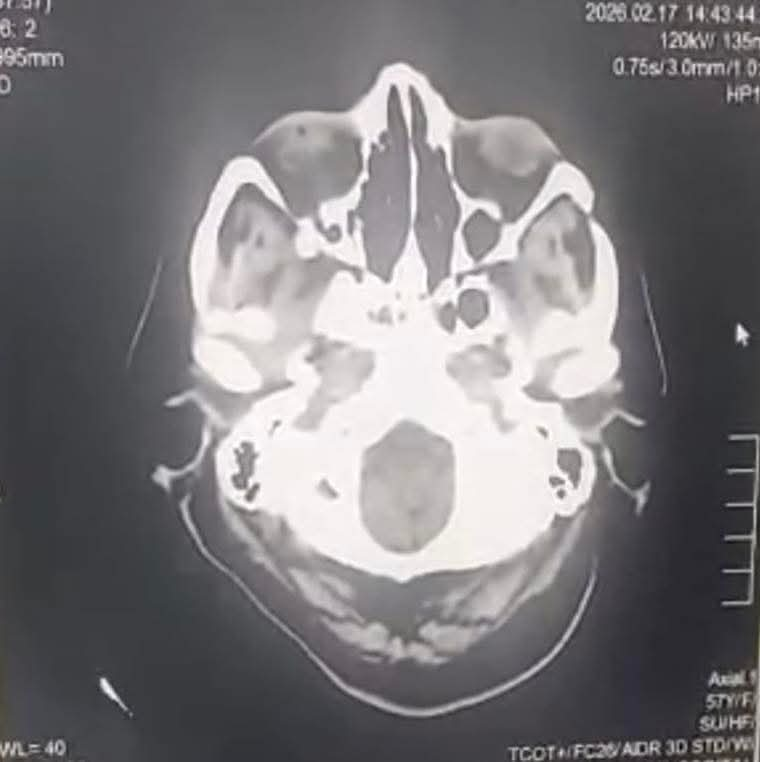

ومن جهته، أوضح الدكتور محمود البرنس، مدير المستشفى، أن المريضة حضرت إلى قسم الطوارئ وهي تعاني من ضعف حاد بالجانب الأيسر من الجسم، وتلعثم في الكلام، واضطراب بالحركة والإحساس، دون وجود تاريخ مرضي سابق يُذكر. وعلى الفور، تم تفعيل بروتوكول السكتة الدماغية المعتمد، وإجراء التقييم الإكلينيكي الشامل والفحوصات الإشعاعية اللازمة.